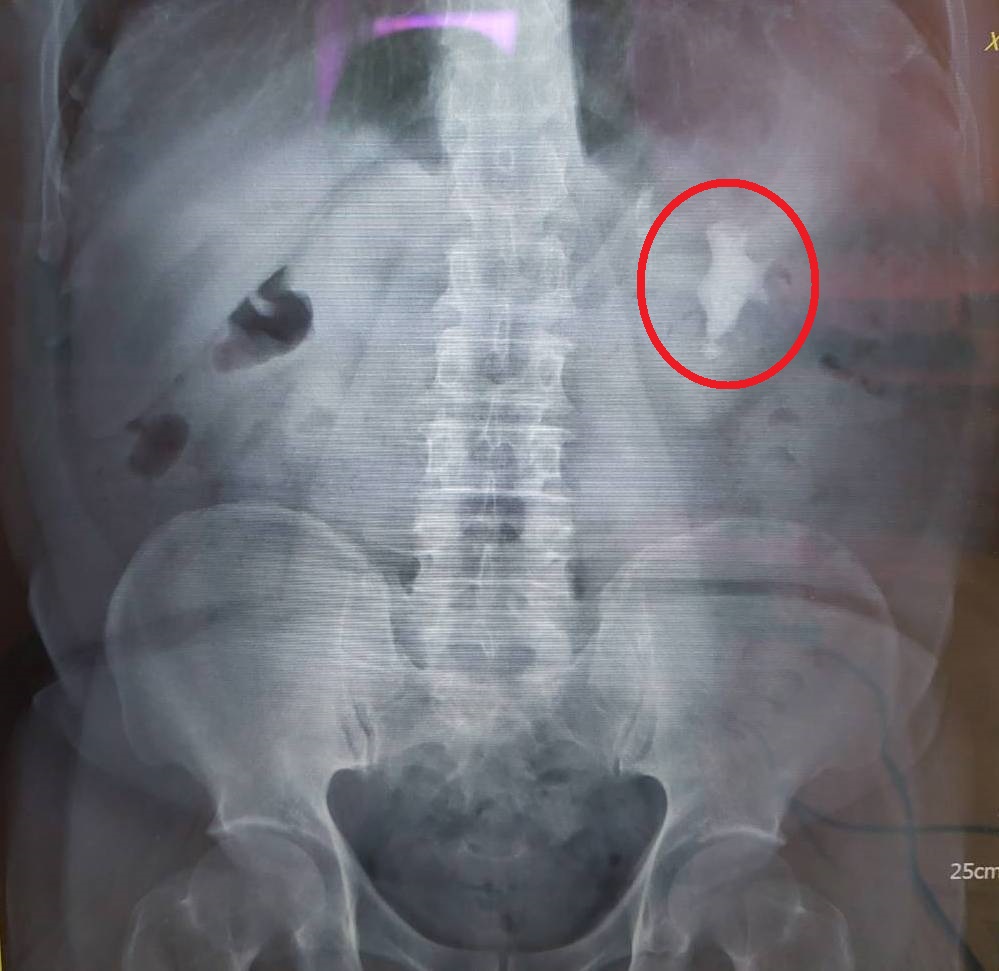

經X光檢查發現,病人的左腎有一個4公分大的鹿角結石(紅圈處)。

70歲的黃先生因腹部脹痛而至醫院就醫,經腹部超音波檢查發現左腎有結石,且有血尿的情況,進一步安排X光檢查,確認左腎有一個約4公分長、2公分寬的鹿角結石。比對三年多前的X光報告,當時尚未形成此結石,判斷是因細菌感染造成的「感染性腎結石」,才會讓結石如此快速長大。